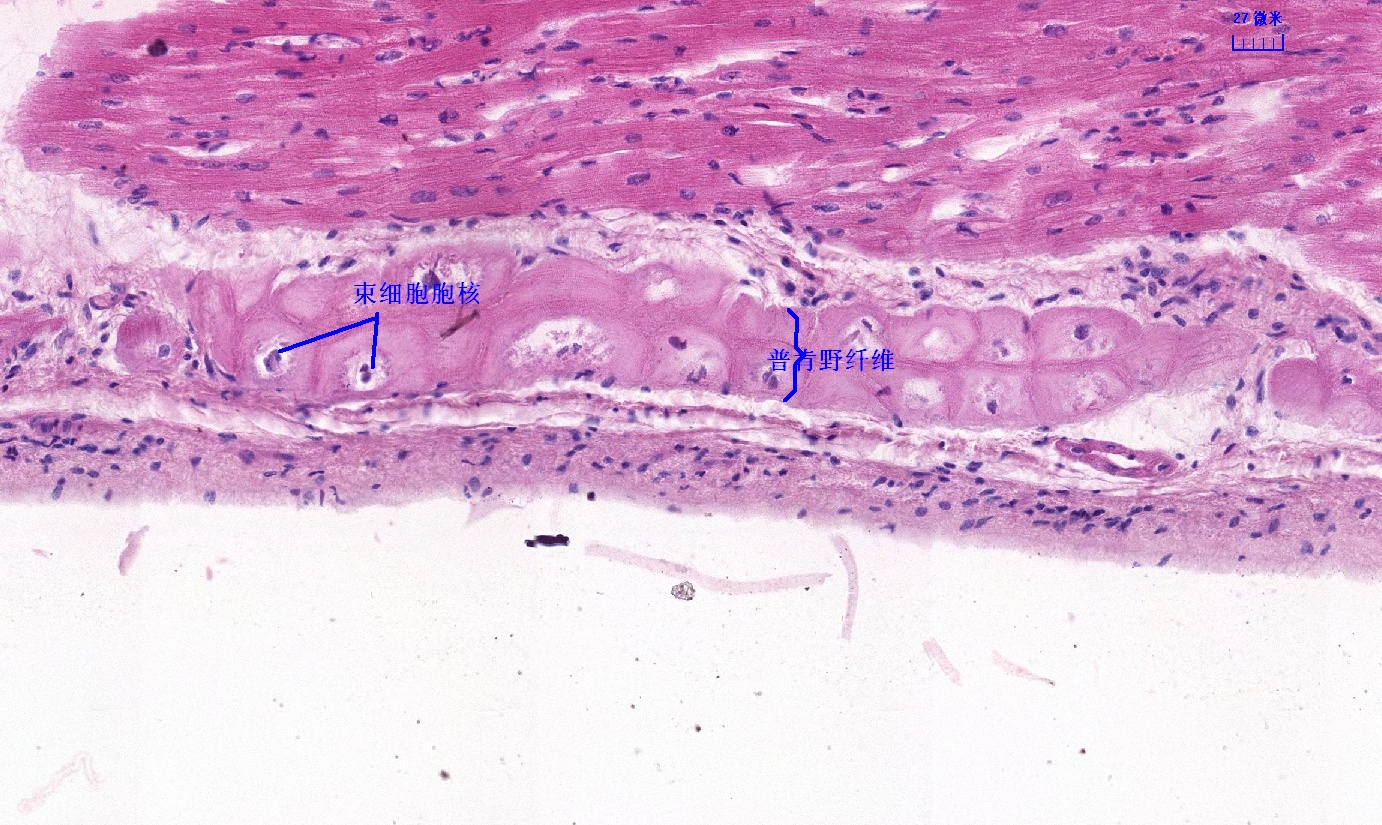

6.1 循环系统切片库

6.2 循环系统微课

6.3 循环系统课件